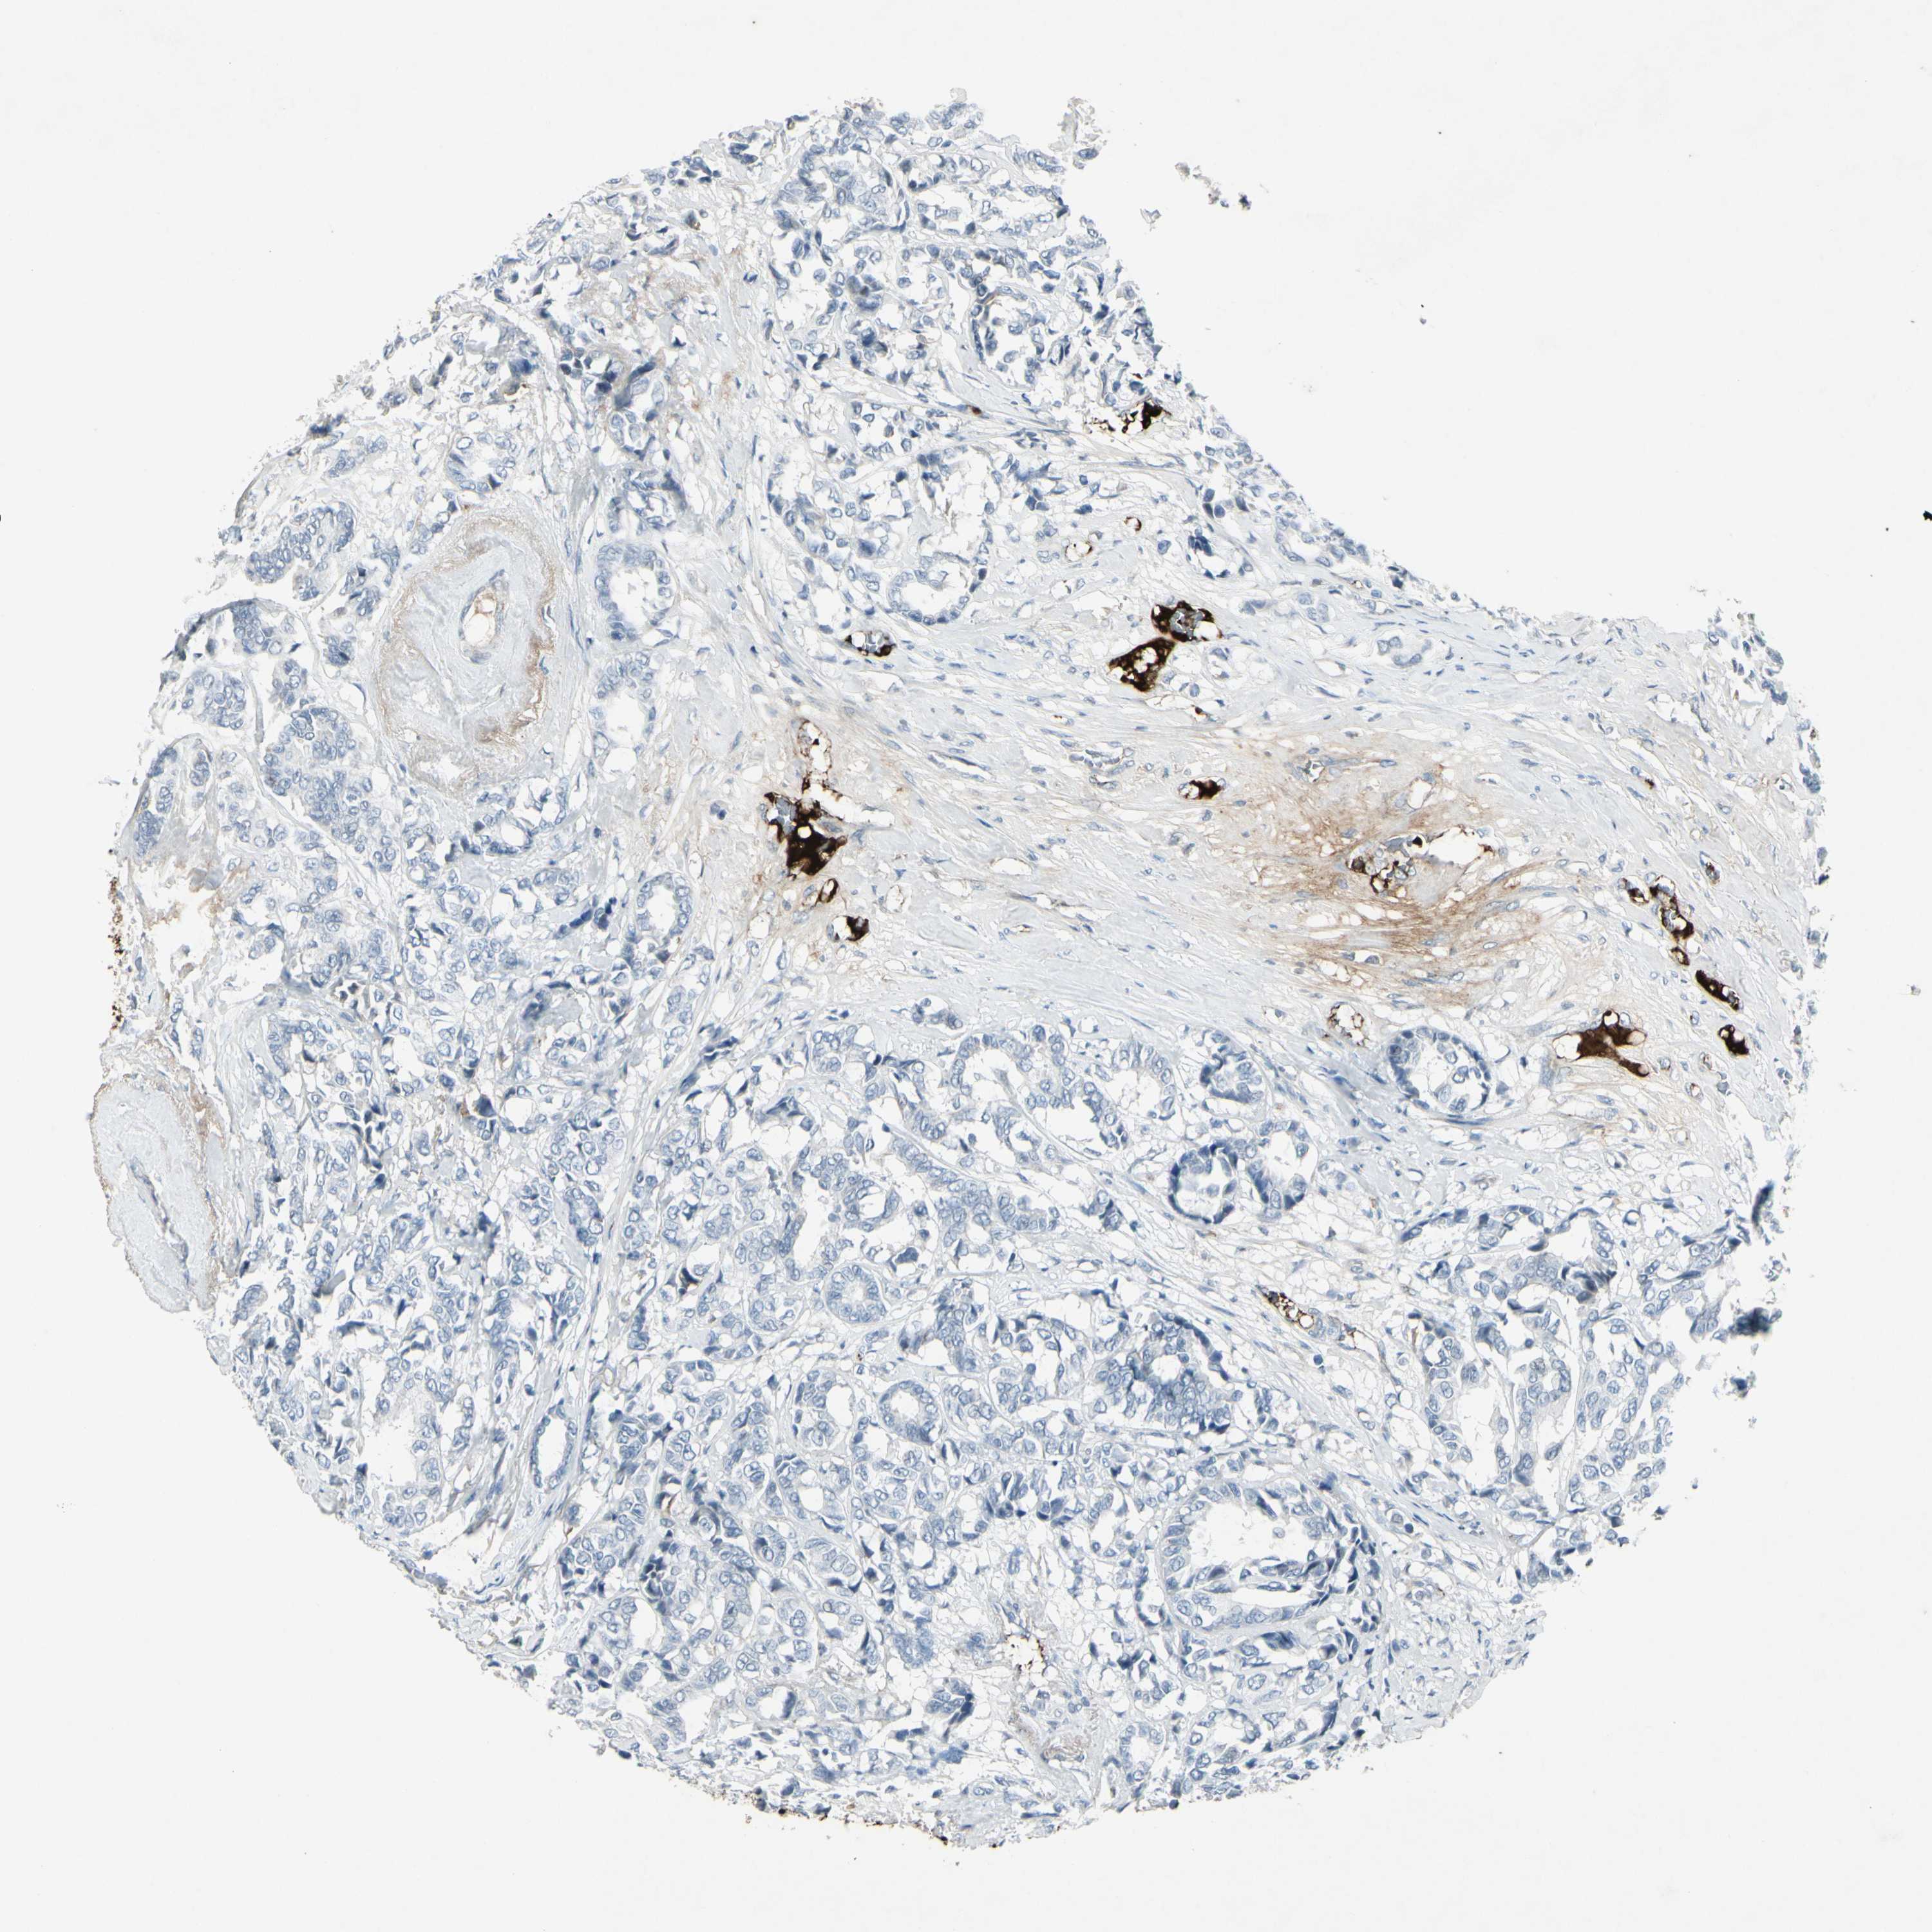

CANCER BREAST CANCER Show tissue menu

BRCA TCGA BRCA VALIDATION PROTEIN EXPRESSION

IGHM is potential prognostic, high expression is favorable in Breast Invasive Carcinoma (TCGA)

Average pTPM 264.1

Number of samples 1022